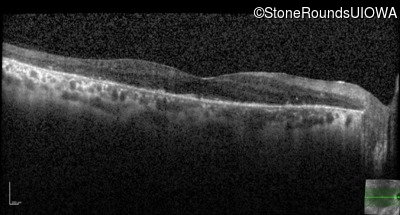

Optical Coherence Tomography - Right - 20/40 +2

Exemplar / OCT Stack

OCT Stack

Optical Coherence Tomography - Left - 20/100 +1